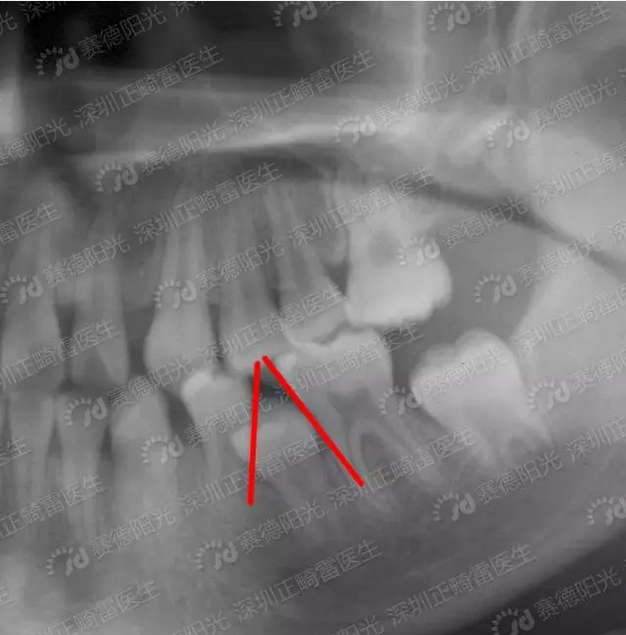

长智齿怎么办,“智齿”是指人类口腔内,牙槽骨上最里面的上下左右各一的四颗牙齿。一般在成年后开始萌出,

健康咨询描述:长了个大牙 曾经的病情分析: 你好,你的这种情况是智齿萌出,智齿一般多在18-24岁左右长出

患者信息:女24岁河北邯郸病情描述展开全部 智齿的生长,关键看你牙床的位置、颌骨的空间是否够,如果够,